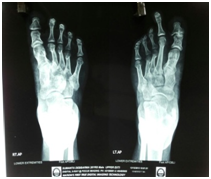

Figure 5 X ray feet: Right 4th and 5th metatarsal short and left 2nd,3rd, and 4th metatarsal short.